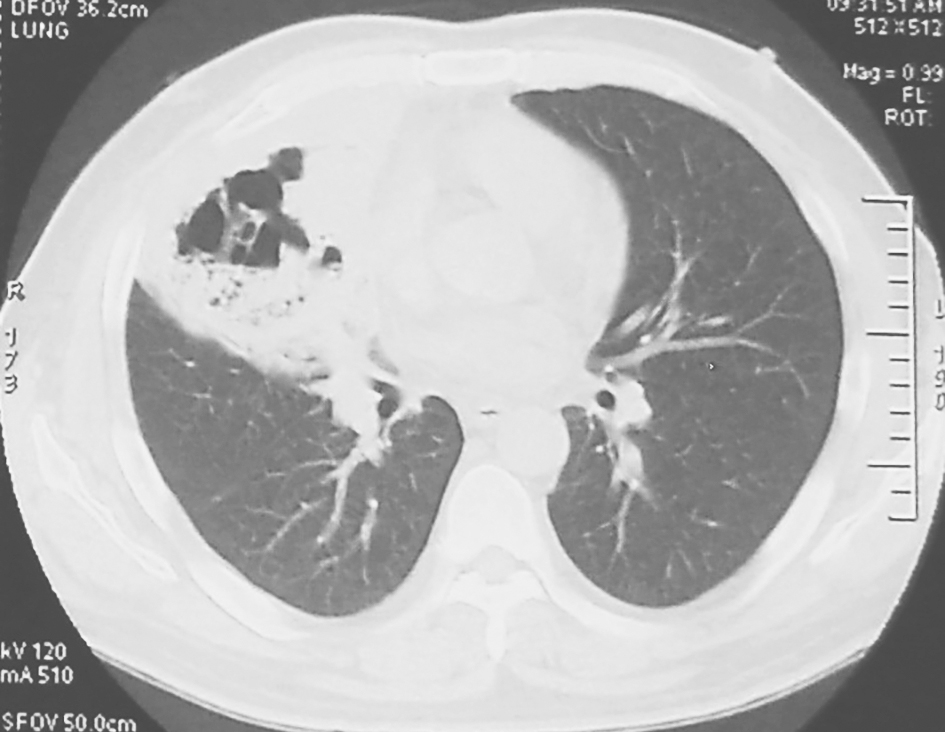

图3 胸部CT表现(2011-02-09)

胸部CT可见右肺实变影较前增大,并出现不规则厚壁空洞